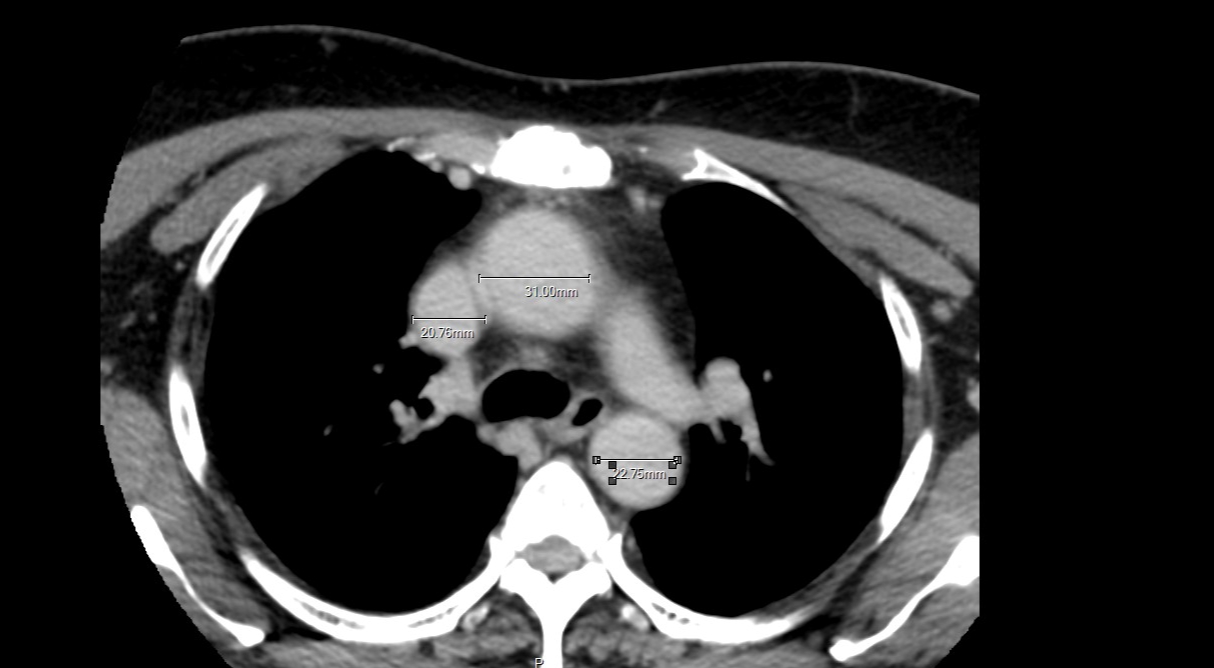

คุณแม่เป็นมะเร็งไทรอยด์ (papillary Thyroid Carcinoma) ระยะที่ 3-4 คือลามไปต่อมน้ำเหลืองแล้ว ต่อมน้ำเหลืองขนาด4-5 เซน ประมาณไข่ไก่เบอร์0 คุณหมอบอกแบบนั้น ตอนนี้แม่กับเราเดินมาถึงปลายอุโมงค์แล้ว คือการรอผ่าตัด